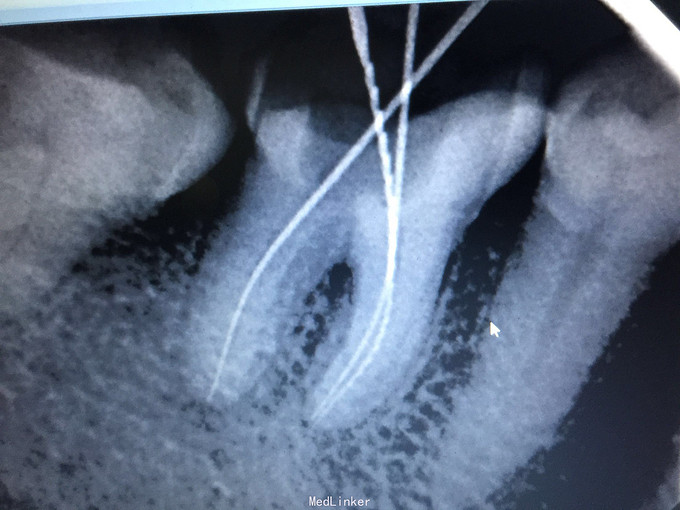

检查:46牙合面重度磨耗近髓,叩诊(+-),松动无,牙龈无明显红肿,冷诊(++)。 X线示:46牙合面缺损近髓腔,根尖无明显低密度影像。

诊断:46急性牙髓炎 治疗:46局麻下开髓揭顶全,慢失活,暂封,肿痛随诊。 二诊:46去暂封及失活剂,根管长度测量,根管预备,冲洗,干燥,根管消毒,根充,适充,锌基,树脂充填,调合,抛光,告医嘱。 建议46冠修复。